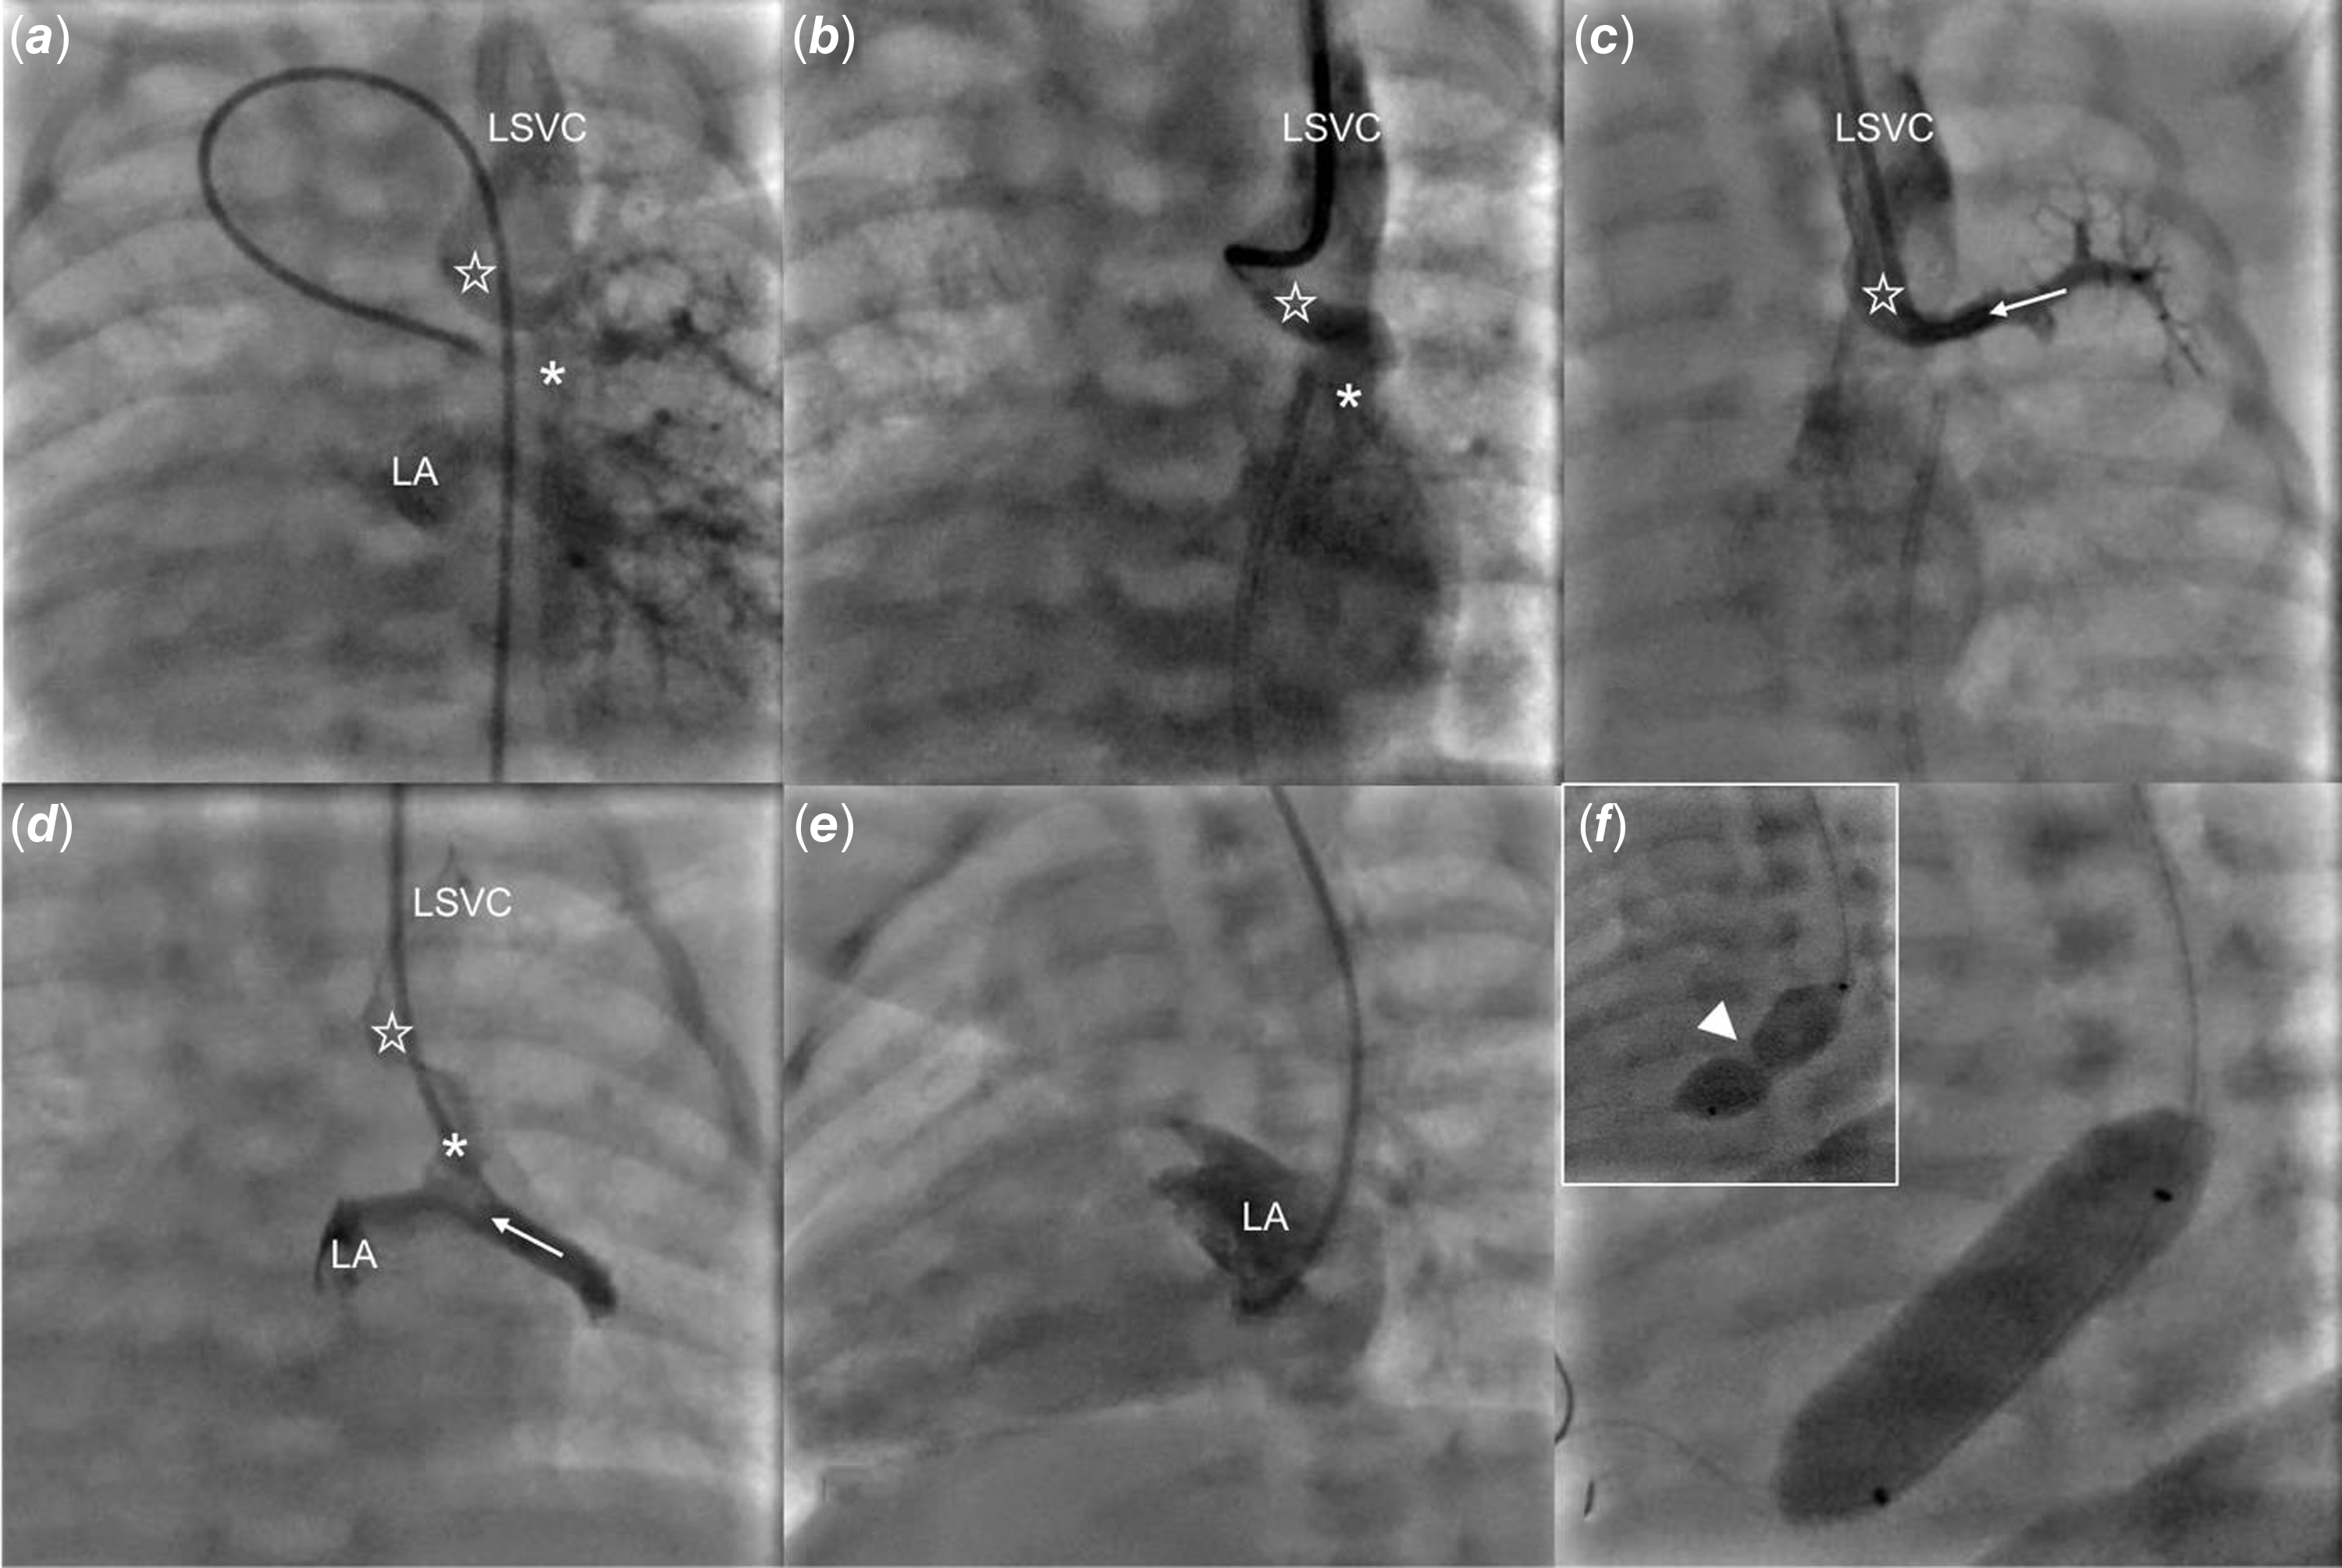

Under general anaesthesia and guided by ultrasound, vascular access was obtained through the left internal jugular vein and the right femoral artery. A 4 Fr angiographic catheter was advanced through the ductus arteriosus to the left pulmonary artery. Angiography in the late venous phase revealed an unobstructed anomalous pulmonary vein drainage from the left upper pulmonary vein to the left superior vena cava, with faint contrast flow between the left upper and middle veins with the latter emptying into the left atrium (Figure 2(a), Supplementary Video 1). Subsequently, hand contrast injections in the vertical vein and the upper and lower pulmonary veins were performed (Figure 2(b), (c) and (d)). Over a 0.014” floppy wire, a catheter was advanced from the left superior vena cava, through the vertical vein, to the left atrium and oriented towards the narrow interatrial communication (Figure 2(e)). Using transthoracic echocardiography and fluoroscopy guidance, the restrictive interatrial communication was crossed downstream and static atrial septoplasty using a 10 x 30 mm Tyshak II balloon (NuMed) was performed. The catheter was inflated twice, with a clear indentation on the first attempt and full expansion during the second (Figure 2(f), Supplementary Figure 1E, Supplementary Video 1). Haemodynamic measurements showed a mean left atrial pressure of 8 mmHg, with a mean gradient across the atrial septum of 1 mmHg. Transthoracic echocardiography confirmed unrestrictive flow through the interatrial communication (Supplementary Figure 1F).

Figure 2. Percutaneous static balloon atrialseptoplasty. ( a ) a late phase of angiography from the left pulmonary artery shows contrast return from the left lung to the left superior vena cava (LSVC) via a vertical vein (empty star) and to the left atrium (LA). ( b ) a hand contrast injection to the vertical vein (empty star) through a catheter advanced from the LSVC. ( c ) angiography from the left upper pulmonary vein (white dotted arrow) shows contrast return via the vertical vein (empty star) to the LSVC. ( d ) an angiography through the catheter advanced further through a connection (asterix) between the left upper and middle (white arrow) veins shows simultaneous contrast flow to the left atrium and LSVC. ( e ) an angiography from the LA with minimal flow across the inter-atrial septum to the right atrium. ( f ) arrowhead points to the indentation on the balloon catheter at the beginning of inflation that vanished with complete balloon expansion.